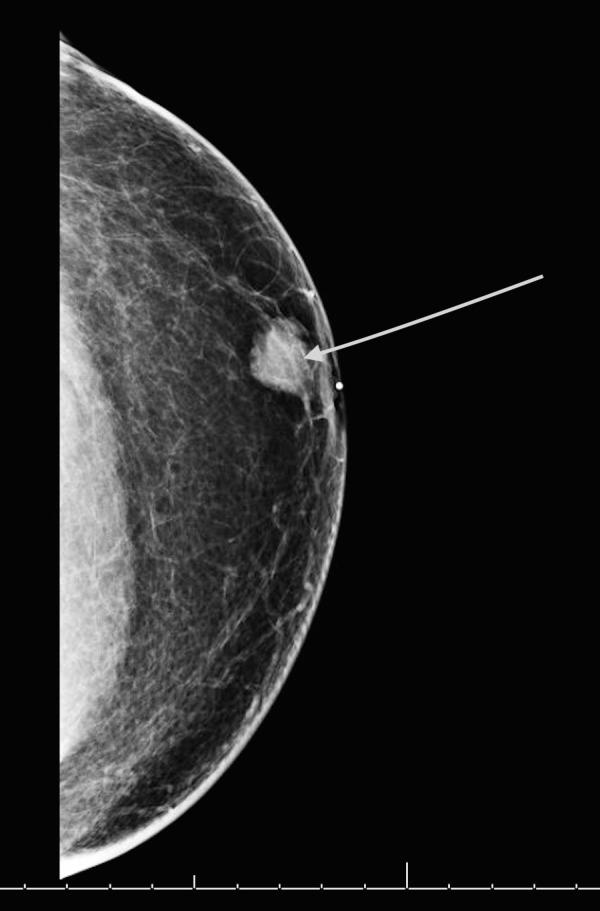

Image of a diagnostic mammogram showing a breast mass in a male patient.

Diagnostic mammogram showing a left breast mass in a male patient.

Credit: Cureus July 2017. doi 10.7759/cureus.1481. CC BY 3.0.